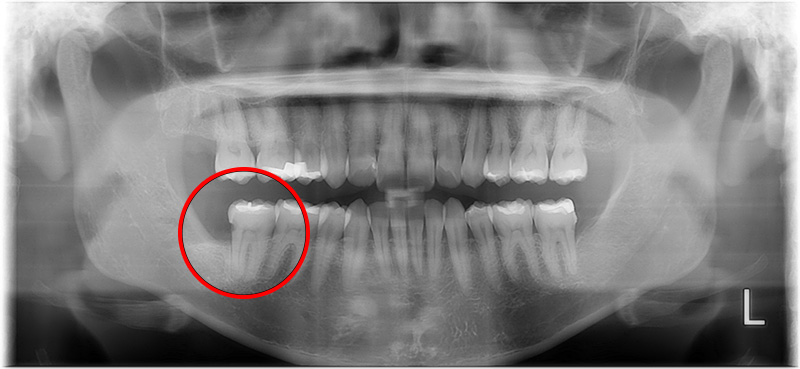

before

| ■性別・年代 | 女性・40代 |

|---|---|

| ■治療内容 | 汚れが溜まり虫歯があり右下の親知らずを抜歯しました。 |

| ■金額 | 埋伏抜歯 5,120円 CT 4,400円 |

| ■治療期間 | 1日 |

| ■通院回数 | 1回 |

| ■リスク・副作用 | 抜歯後にしびれが出ることや、まれに腫れや痛みが長引くことがあります。 |